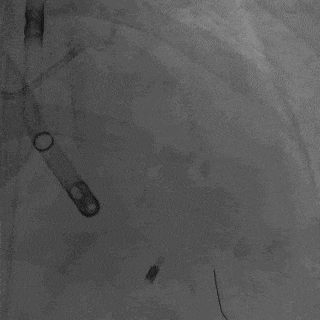

造影结果显示,患者存在严重的三支病变情况:前降支中段狭窄达到90%,回旋支完全闭塞,可见自身侧枝逆向供血至远端;右冠状动脉全程弥漫重度狭窄,且远端闭塞。

经皮左心室搏动泵置入

患者经历了右髋关节置换术后,左心搏动泵得以从左侧股动脉入路顺利置入。浙江大学医学院附属第二医院心内科蒋峻主任首先用CTO导丝尝试开通回旋支闭塞病变,但由于患者长期患有糖尿病和肾功能不全,病变坚硬,导丝通过困难。考虑到患者正处于心衰急性期且肾功能不全,蒋峻教授迅速调整了治疗策略,优先处理前降支病变,预扩张后快速植入支架。